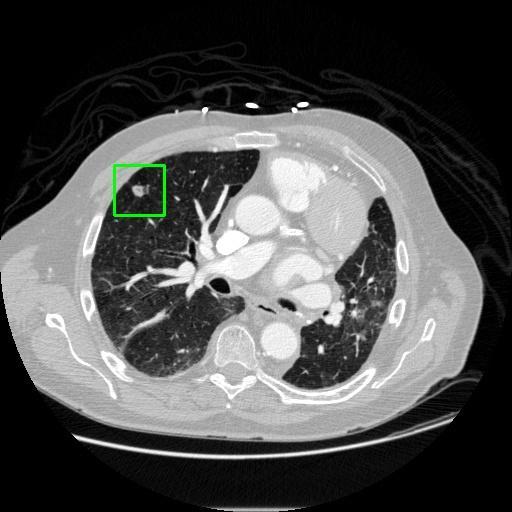

We developed an AI-based system using deep learning models for analyzing lung CT scans to detect and classify pulmonary nodules. We chose the YOLOv11 architecture for its enhanced object detection capability and adapted it specifically for medical imaging, incorporating pixel-level precision and severity classification.

Classification into three severity levels with colored bounding boxes.

Designed a severity classification system that categorizes nodules into null, moderate, and severe using colored bounding boxes, assisting in rapid clinical decision-making.